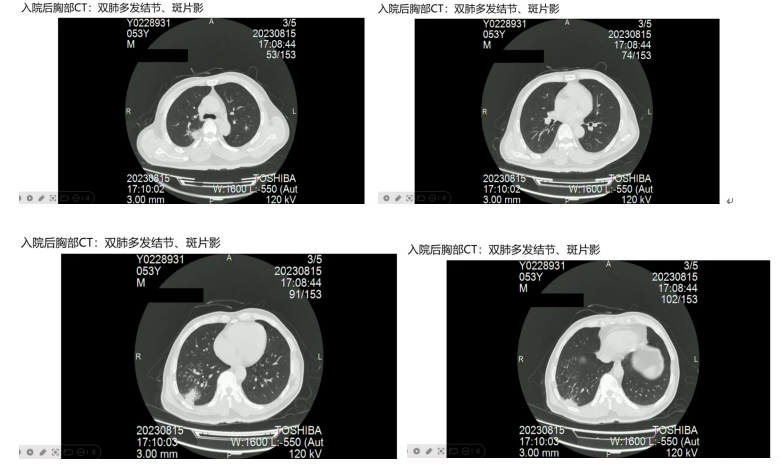

胸部CT显示双肺多发结节、斑片状影,右下肺空洞样病变较前实变;头颅增强MRI提示左侧额叶脑室多发脓肿病灶且脓肿壁强化;浅表淋巴结超声提示腹股沟和腋窝多发肿大淋巴结。